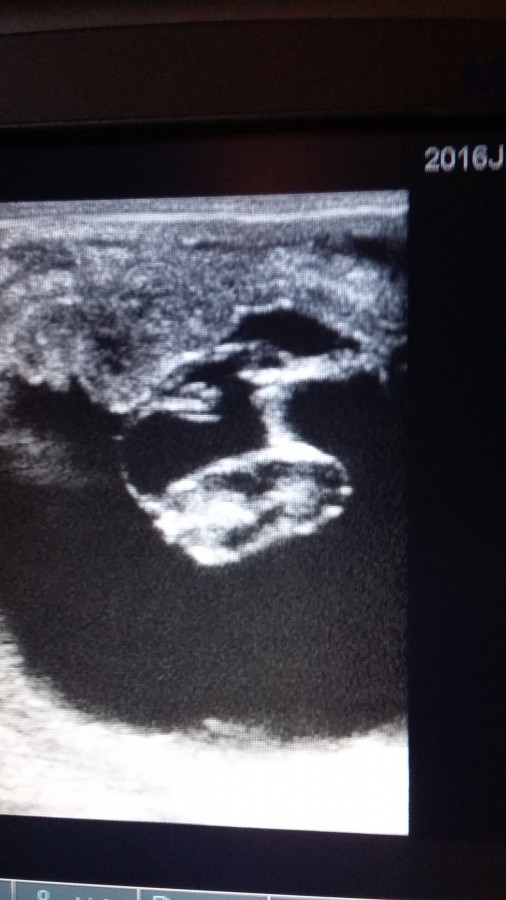

moi, avec tout vos soucis de juments qui coulent après 15 jours, j'ai refait une écho de contrôle...

ma ponette est donc toujours pleine ce jour de 35 jours environ.